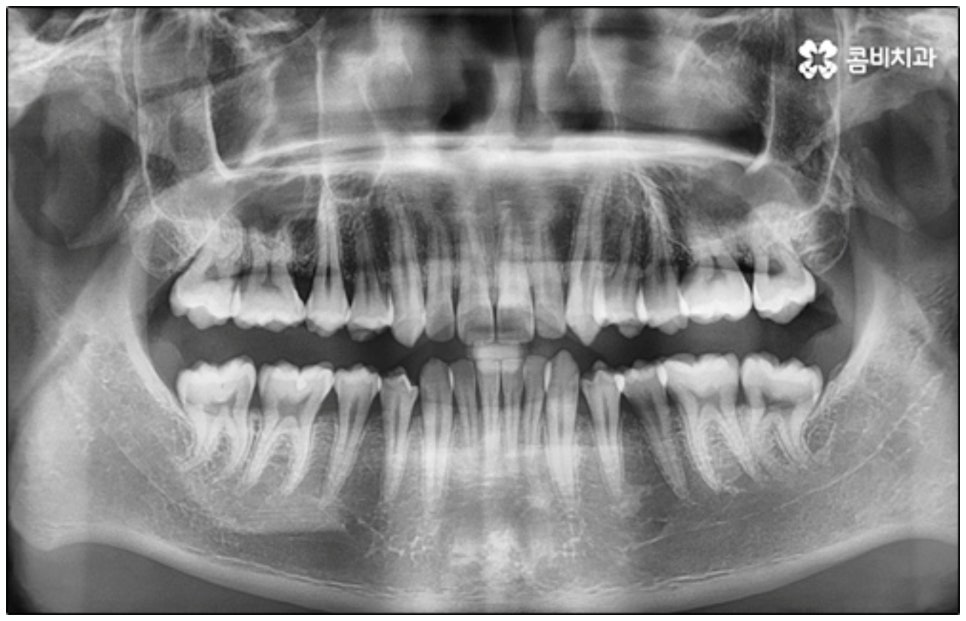

말씀드린 것과 같은 다양한 이점들이 있기 때문에 현재 본원의 교정 환자분들은 대부분 클리피씨교정 장치를 이용하여 치료를 진행하고 있습니다. 사진 역시 돌출입 교정을 위해 발치 후 클리피씨교정 장치를 이용하신 환자분의 케이스인데 시간이 지날수록 점차 앞니가 자연스럽게 들어가고 위아래 교합이 정확하게 맞아가는 것을 확인하실 수 있을 거예요.